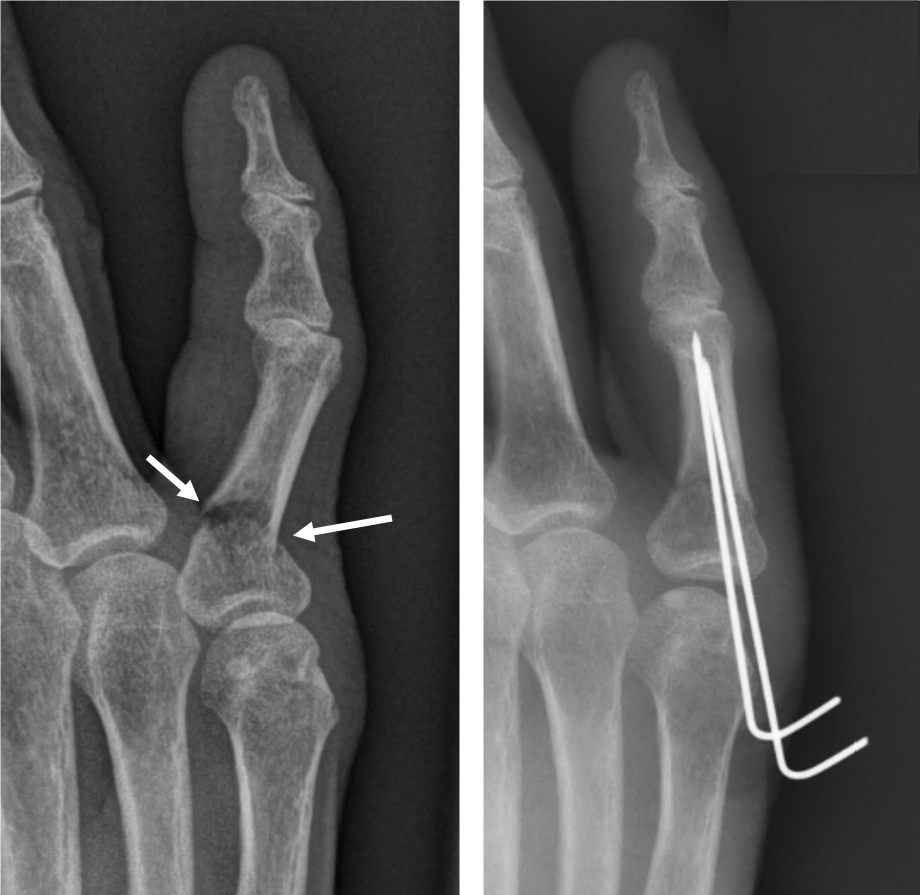

- 수술: 복합 골절이나 압박 골절의 경우에는 핀을 박는 수술이 필요할 수 있습니다.

- 금속판 사용: 뼈가 조각나거나 비스듬하게 부러진 경우에는 금속판을 덧대어 고정하기도 합니다.

- 복합 골절: 뼈가 여러 조각으로 깨져 있는 경우에는 핀이나 금속판을 사용하여 뼈를 고정해야 할 수 있습니다.

- 비스듬한 골절: 뼈가 비스듬하게 부러진 경우에도 핀을 사용하여 고정하는 것이 일반적입니다.